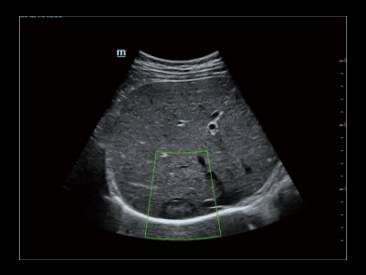

Inteligentna ocena st?uszczenia w?troby poprzez automatyczne obliczanie stosunku jasno?ci w?troby do kory nerek w trybie B.